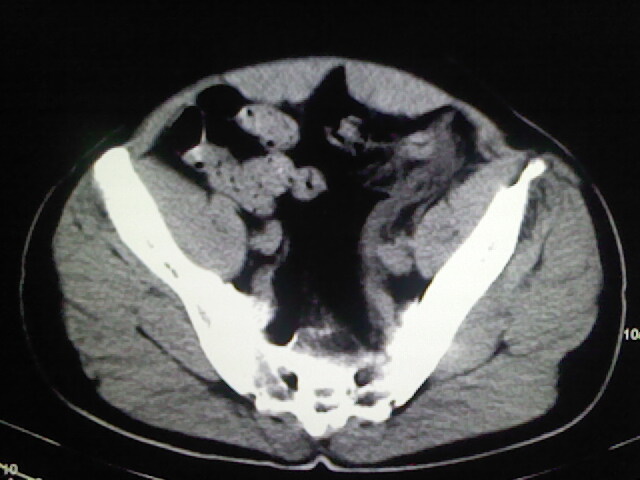

以下是引用zsl6918在2009-2-7 7:29:00的发言:[br]请提供介入的方式方法,肾及输尿管改变考虑与介入损伤有关,漏了,尿液外渗。

以下是引用余辉在2009-2-7 8:27:00的发言:[br]可能是硬化剂烧穿囊壁进入肾盂输尿管了,尿漏。不除外介入或碎石术后合并感染[br]患者术后怀疑结石,接着就碎石了?就怀疑没有确诊吗?碎石用的什么方法?气压弹道还是体外超声?如果这样的话责任人都难找

以下是引用随光逐影在2009-2-7 8:46:00的发言:[br]支持3楼意见。[br]另:不排除左肾及肾周感染可能。